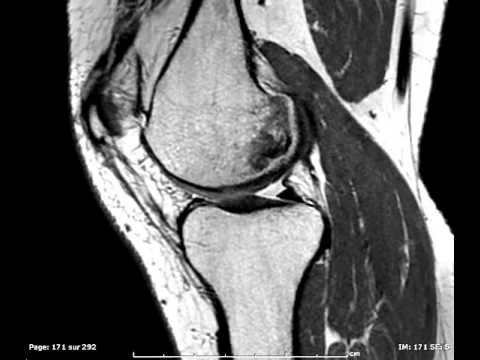

L’IRM des Articulations Temporo-Mandibulaires permet d’étudier le positionnement du ménisque entre le condyle mandibulaire et le versant temporal de l’articulation de façon dynamique.

Il s’agit d’un examen dynamique où plusieurs acquisitions seront faites à différents degré d’ouverture buccale (occlusion, 5 mm, 10 mm et ouverture maximale). Pour cela une petite cale sera placée entre vos incisives pour faciliter la mise en place des différents degrés d’ouverture.